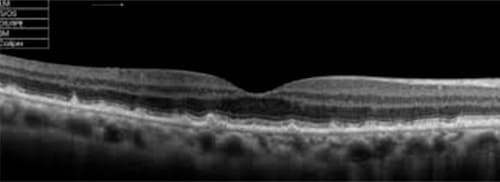

•Tomografia de coerência óptica (OCT)